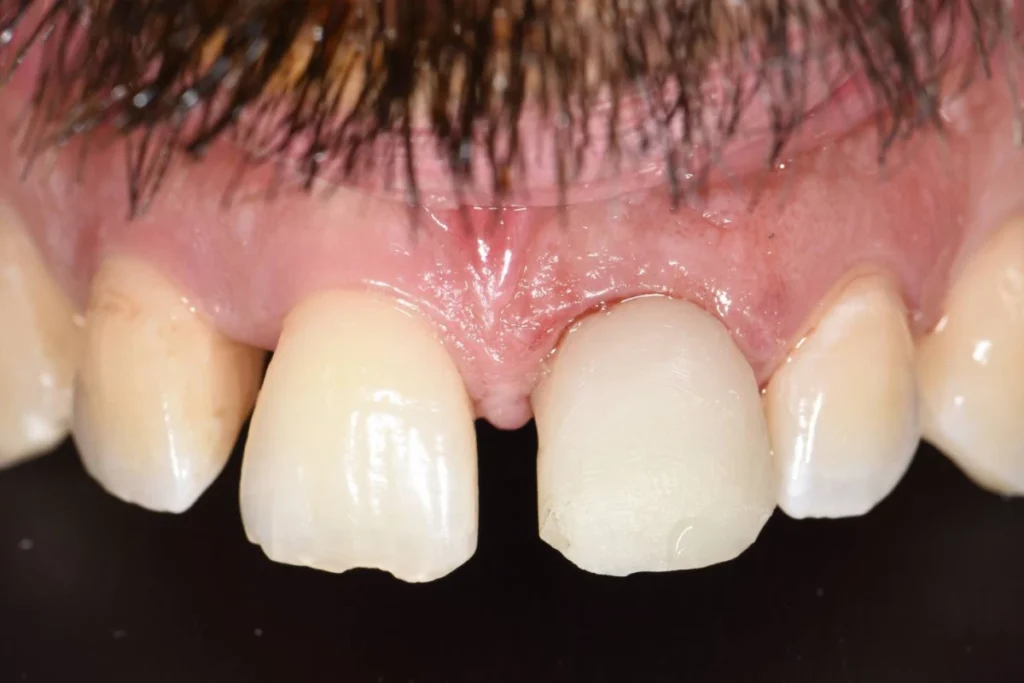

Cas clinique 2 – Remplacement d’une incisive latérale par un implant dentaire

Mr C. 40 ans vient nous consulter pour une visite de routine. L’examen clinique et met en évidence un infection sous une dent couronnée il y plusieurs années par un confrère. Le scanner réalisé au cabinet confirme la nécessité d’extraire cette dent et nous décidons de réaliser un protocole d’extraction implantation et mise en esthétique immédiate.

En clair, nous réalisons l’extraction de la dent, la mise en place de la racine artificielle ou implant et la fabrication d’une couronne provisoire en résine le tout lors de la même séance. Le patient repart du cabinet avec toutes ses dents!

Dans le cas présent, nous avons même pu répondre à la demande esthétique du patient en symétrisant son incisive latérale droite avec celle de gauche. L’intervention est réalisée sous anesthésie locale ce qui la rend parfaitement indolore.

Ce type de protocole est réalisé systématiquement au cabinet lorsque la situation nous le permet afin d’éviter à nos patients la galère d’un appareil provisoire amovible pour remplacer la dent absente. En contrepartie, le patient s’engage à respecter nos recommandations post opératoires pendant les semaines qui suivent l’intervention.